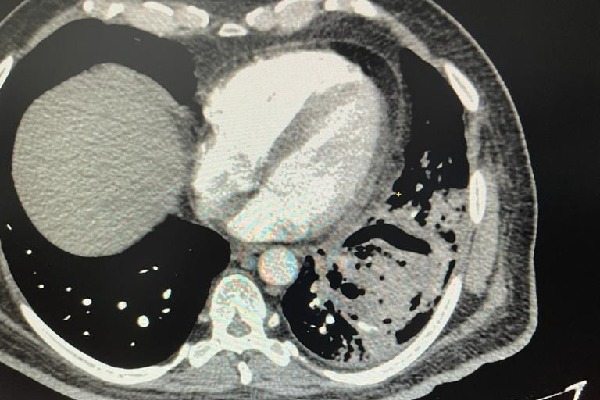

The patient, Mr. Rama Nageshwar Rao, was rushed to SLG Hospitals on 10th July, after he started coughing blood due to a severe cough. CT scan revealed acute damage caused to the lower lobe of the left lung, along with a deep cavity in it. A presumptive diagnosis of the condition was the post-Covid lung damage or cavity in the lung due to past Covid-19 infection caused in the month of May this year.

Commenting on the condition and treatment administered, Dr. Vivek Babu Bojjawar, Consultant Cardiothoracic & Vascular Surgeon, SLG Hospitals said, “Aspergilloma is normally noticed among people with the weak immune system. While this is commonly found among patients suffering from tuberculosis, finding it as an after-affect of Covid-19 infection is a first! This condition damages the lungs causes the cavity and could result in a fatality at an advanced stage. Vomiting blood by Mr. Rao is an indication the spread of this virus is deep and necessitated emergency surgery.”

“A lobectomy surgery was performed on the patient to remove the virus ball along with traces of damaged lung. This condition can be seen as a medium to the long-term side-effect of Covid-19 infection, and such conditions must be traced and treated early before they develop into health emergencies necessitating surgical procedures,” added Dr. Vivek Babu.